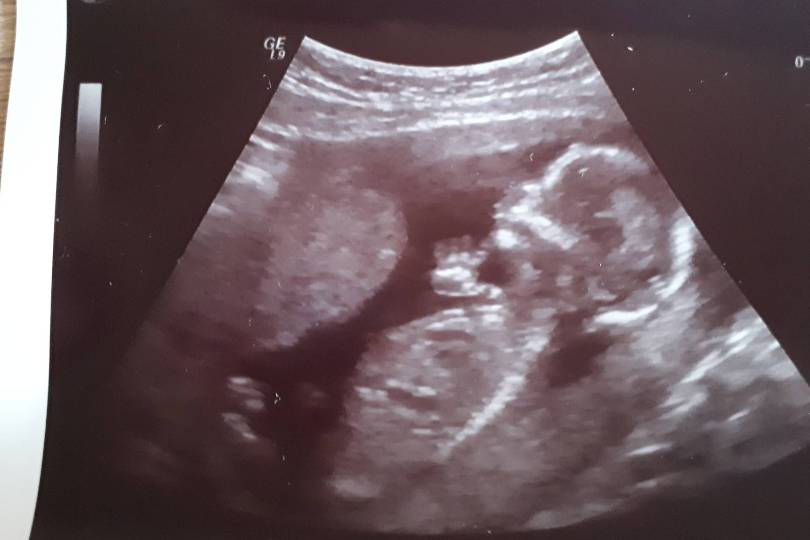

Hej. Dawno się nie udzielalam ale czytam Was cały czas. Chciałam Wam powiedzieć że będę miała chłopczyka

. Intuicja mnie nie zawiodła kolejny raz [emoji5].Zobacz załącznik 850966